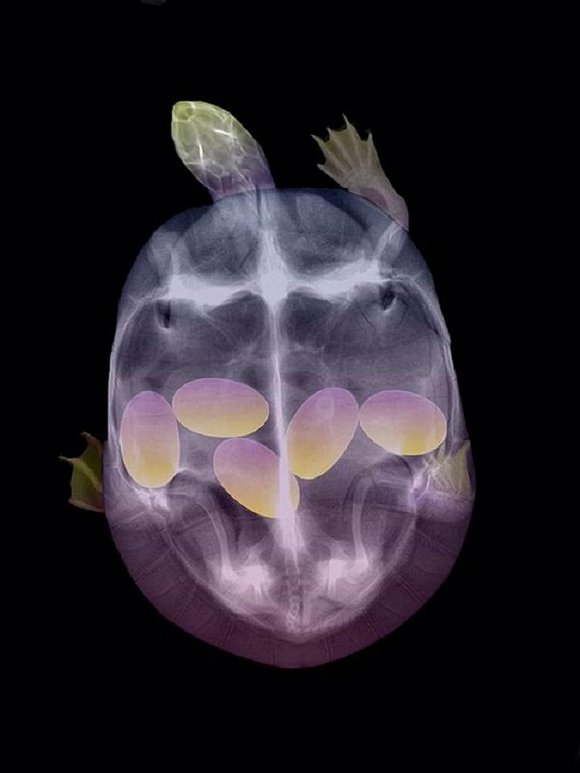

可爱又毛骨悚然 怀孕动物的X光片

人类之间分享母亲肚子里胎儿的X光片是一件非常常见的事情,但是,纵使你觉得自己对X光片已经见怪不怪,在看到了下面这些怀孕动物的X光片后你仍旧会说"哦我的天哪"。

自然总是充满有趣事实,你是否知道在各种怀孕的动物中负鼠的生育速度最快?它们只需要14天就可以分娩,而雌性大象的怀孕时间则长达23个月。现在 吉尼斯世界记录上记载的一次分娩中最大小狗出生数量为24只,而海马的生殖则由雄性负责,一只雄性海马每次平均产出200只幼鱼苗。

以下就是一些动物在怀孕时的X光片。

1. 乌龟